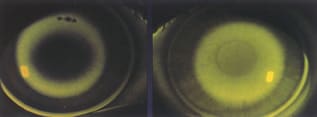

When fitting a lens to achieve corneal reshaping, the ideal lens will have a "doughnut" fluorescein pattern like the one on the left. The lens on the right is too steep and needs to be

flattened. |